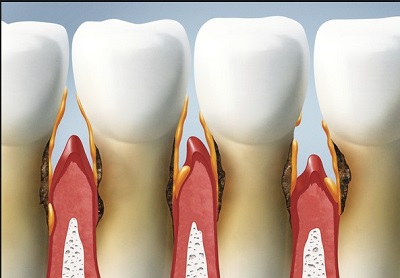

Stadia rozwoju paradontozy Przewlekła choroba atakująca nasze dziąsła i kości

Paradontoza (polska nazwa - bakteryjne zapalenie przyzębia) to przewlekła choroba atakująca nasze dziąsła i kości otaczające zęby.

Ubytki tkanki kostnej wokół zębów w przebiegu paradontozy

Tkanka kostna w zdrowym organizmie podlega ciągłej przebudowie, oznacza to, że taka sama ilość kości powstaje, jak została zresorbowana. Przy paradontozie ubytek kości wokół zębów powstaje wtórnie do stanu zapalnego tkanek miękkich dziąsła i jest wynikiem zaburzenia między procesem nowotworzenia i resorpcji kości. W wyniku drażnienia bakteryjnego tkanek miękkich kieszonki przyzębnej ma miejsce nadmierna stymulacja komórek resorbujących kość. Dochodzi więc do przewagi procesów niszczenia tkanki kostnej, co skutkuje powstawaniem poziomych i rzadziej pionowych ubytków kości. Zauważamy obniżanie wysokości kostnych przegród miedzyzębowych, oraz kostnych przegród międzykorzeniowych u zębów wielokorzeniowych. Rzadziej, u około 10-30% pacjentów dochodzi do powstawania pionowych ubytków kostnych.

Rozwijają się kieszonki kostne, wokół korzeni zębów. Dochodzi również do ubytku kości pomiędzy korzeniami zębów wielokorzeniowych - powstają tzw. ubytki furkacyjne. Poziome ubytki tkanki kostnej są najczęściej rozlane i trudniej poddają się leczeniu. Pionowe ubytki kostne, tzw. kieszonki kostne, można leczyć, wyniki zabiegów regeneracyjnych są bardziej przewidywalne a w zależności od nasilenia zmian chorobowych i czasu w którym choroba została zdiagnozowana i rozpoczęto leczenie można liczyć na skuteczne wyniki zabiegów regeneracyjnych.